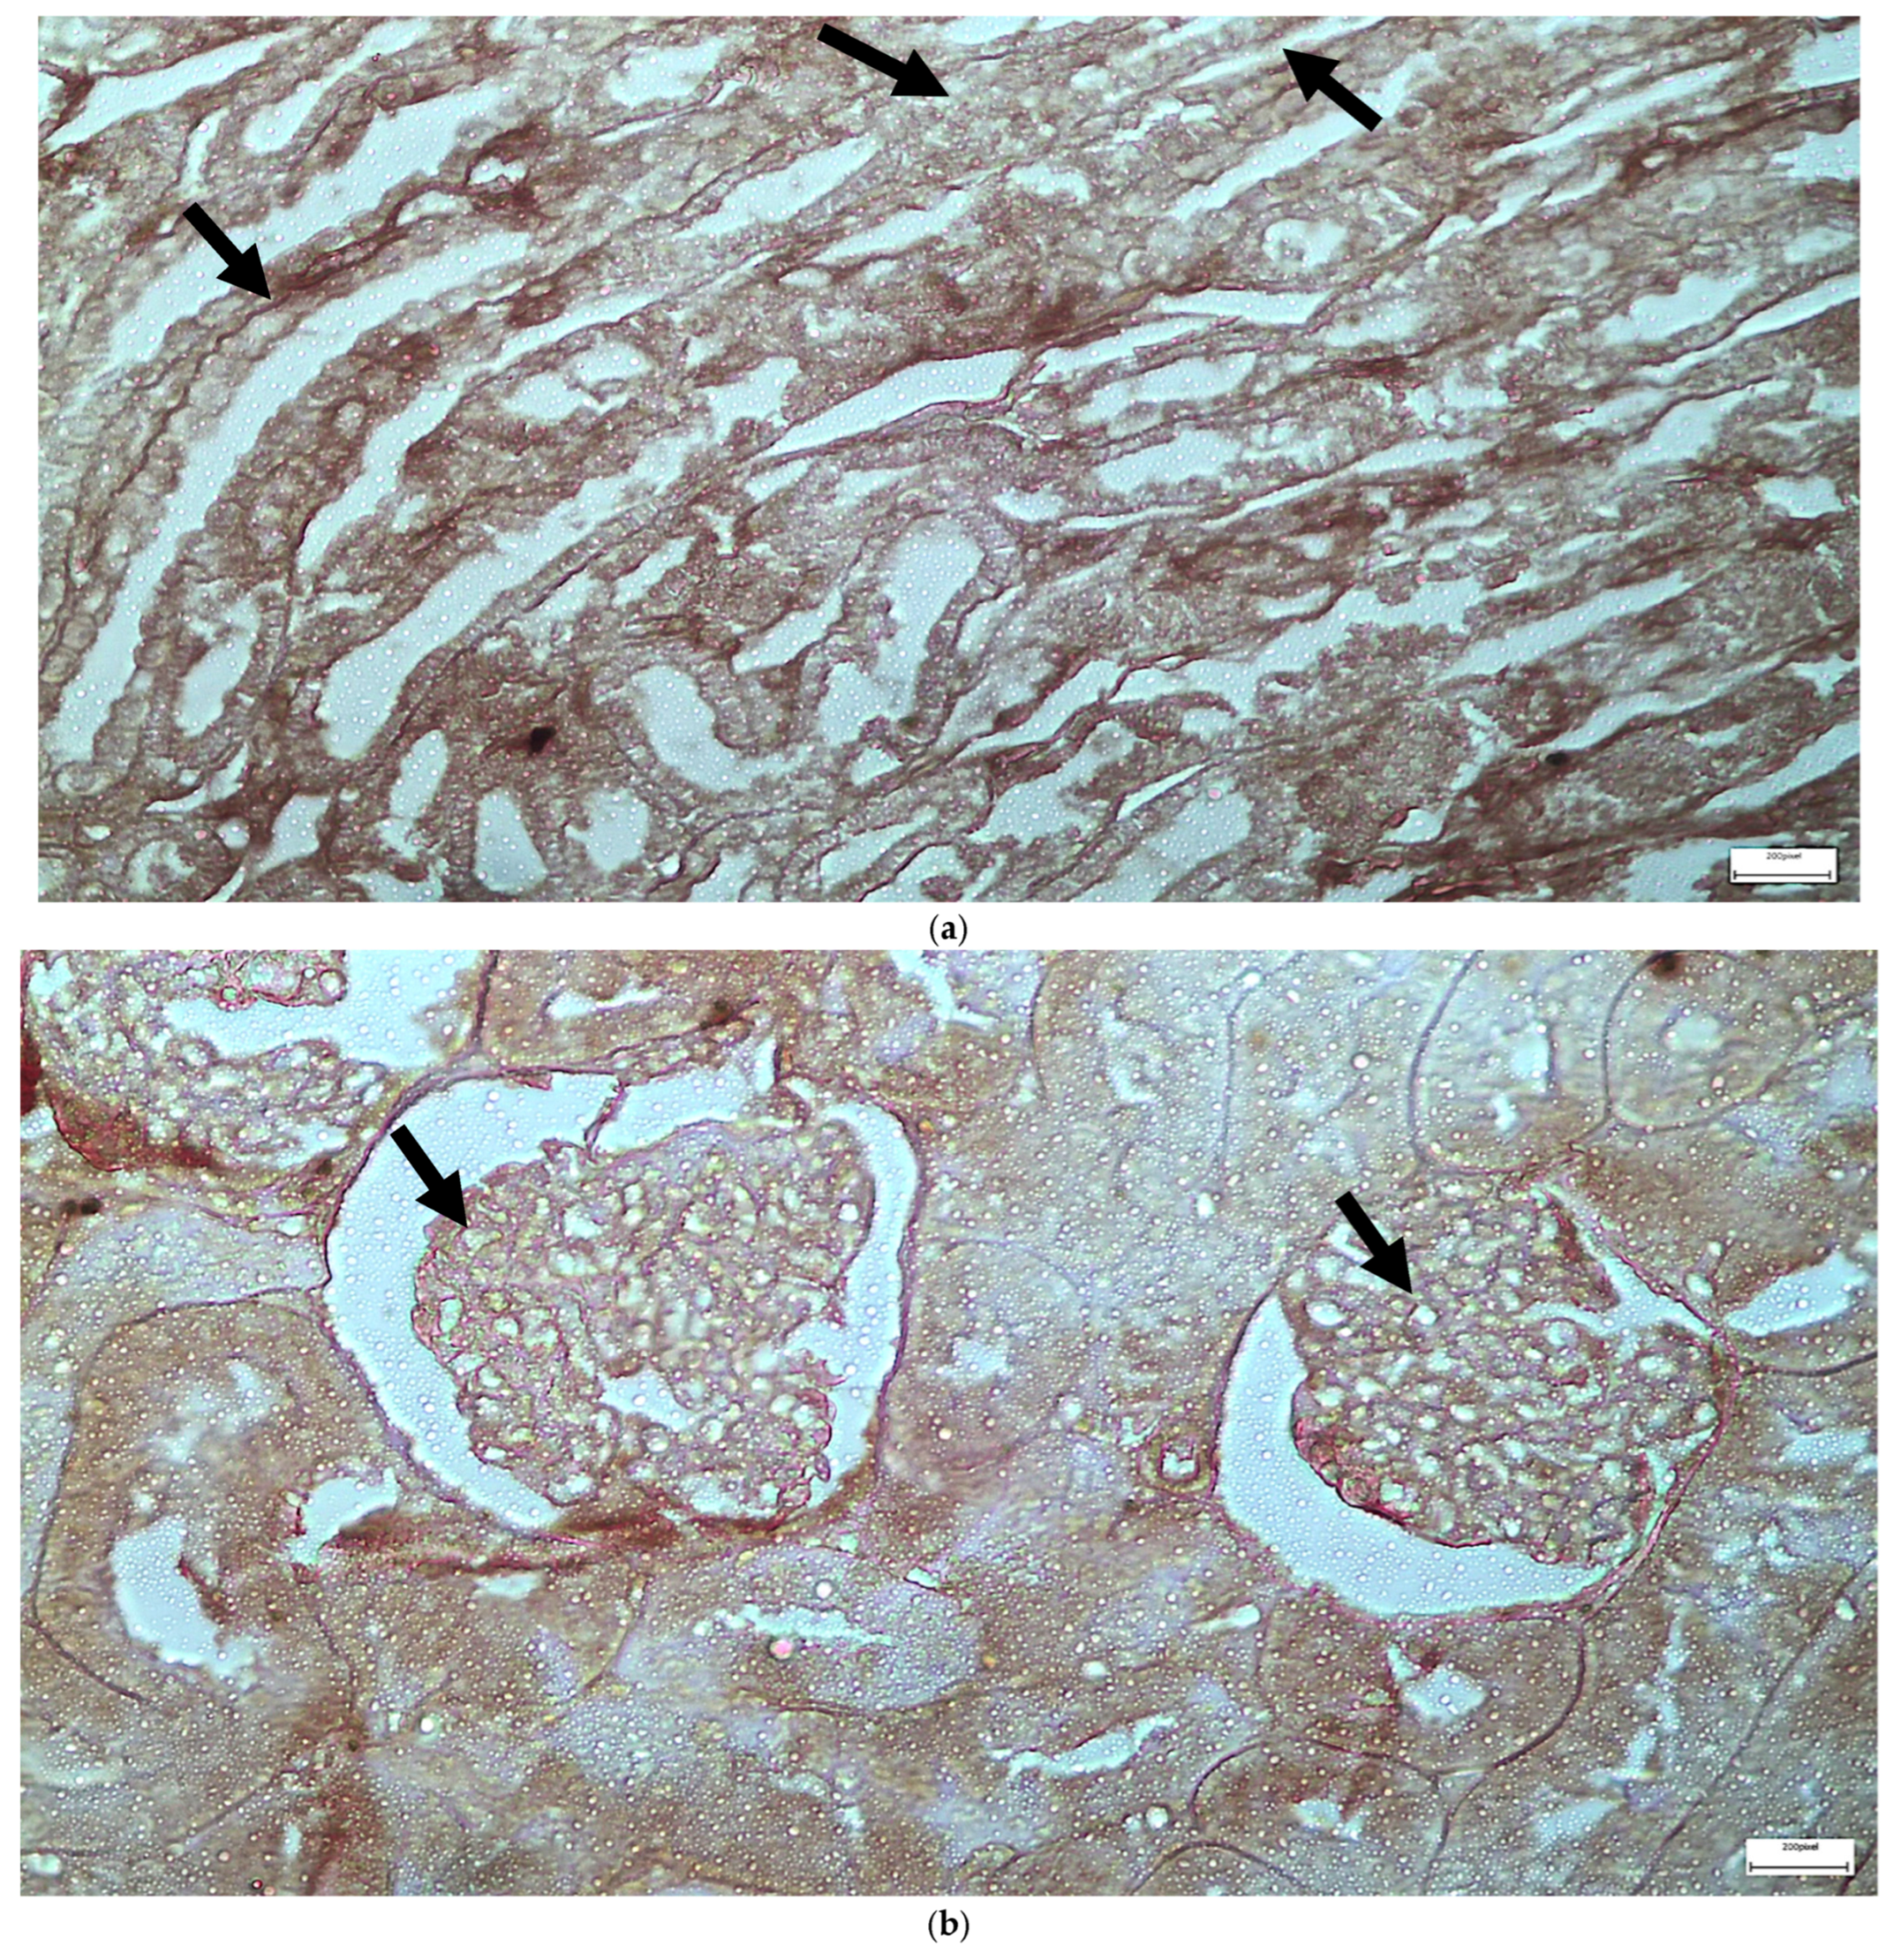

| C | Renal tubules and corpuscles | IL-6 | 1 | 2 | 2 |

| C | Renal tubules and corpuscles | EGFR | 1 | 1 | 1 |

| V1 | Renal tubules | IL-6 | 2 | 4 | 8 |

| V1 | Renal corpuscles | IL-6 | 2 | 2 | 4 |

| V1 | Renal tubules | EGFR | 3 | 4 | 12 |

| V1 | Renal corpuscles | EGFR | 2 | 2 | 4 |

| V2 | Renal corpuscles | IL-6 | 2 | 1 | 2 |

| V2 | Renal tubules | IL-6 | 2 | 3 | 6 |

| V2 | Renal corpuscles | EGFR | 3 | 4 | 12 |

| V2 | Renal tubules | EGFR | 2 | 4 | 8 |

| M1 | Renal corpuscles | IL-6 | 2 | 3 | 6 |

| M1 | Renal tubules | IL-6 | 2 | 1 | 2 |

| M1 | Renal corpuscles | EGFR | 3 | 4 | 12 |

| M1 | Renal tubules | EGFR | 1 | 2 | 2 |

| M2 | Renal corpuscles | IL-6 | 3 | 3 | 9 |

| M2 | Renal tubules | IL-6 | 2 | 3 | 6 |

| M2 | Renal corpuscles | EGFR | 1 | 2 | 2 |

| M2 | Renal tubules | EGFR | 1 | 3 | 3 |

| VM | Renal corpuscles | IL-6 | 3 | 4 | 12 |

| VM | Renal tubules | IL-6 | 1 | 2 | 2 |

| VM | Renal corpuscles | EGFR | 3 | 3 | 9 |

| VM | Renal tubules | EGFR | 2 | 3 | 6 |

| IL-6 | Renal Tubules | 2 (1–4) | 3 (1–5) | 3 (2–5) | 5 (3–6) | 0.048 | VM > C (p = 0.03) |

| Renal Corpuscles | 1 (0–3) | 2 (1–4) | 4 (2–5) | 5 (3–6) | 0.0089 | VM > C (p = 0.006), M > C (p = 0.049) | |

| EGFR | Renal Tubules | 3 (2–4) | 5 (3–6) | 4 (3–6) | 6 (5–7) | 0.0197 | VM > C (p = 0.012), V > C (p = 0.043) |

| Renal Corpuscles | 3 (2–4) | 4 (3–5) | 5 (4–6) | 6 (5–7) | 0.0247 | VM > C (p = 0.013), M > C (p = 0.038) |